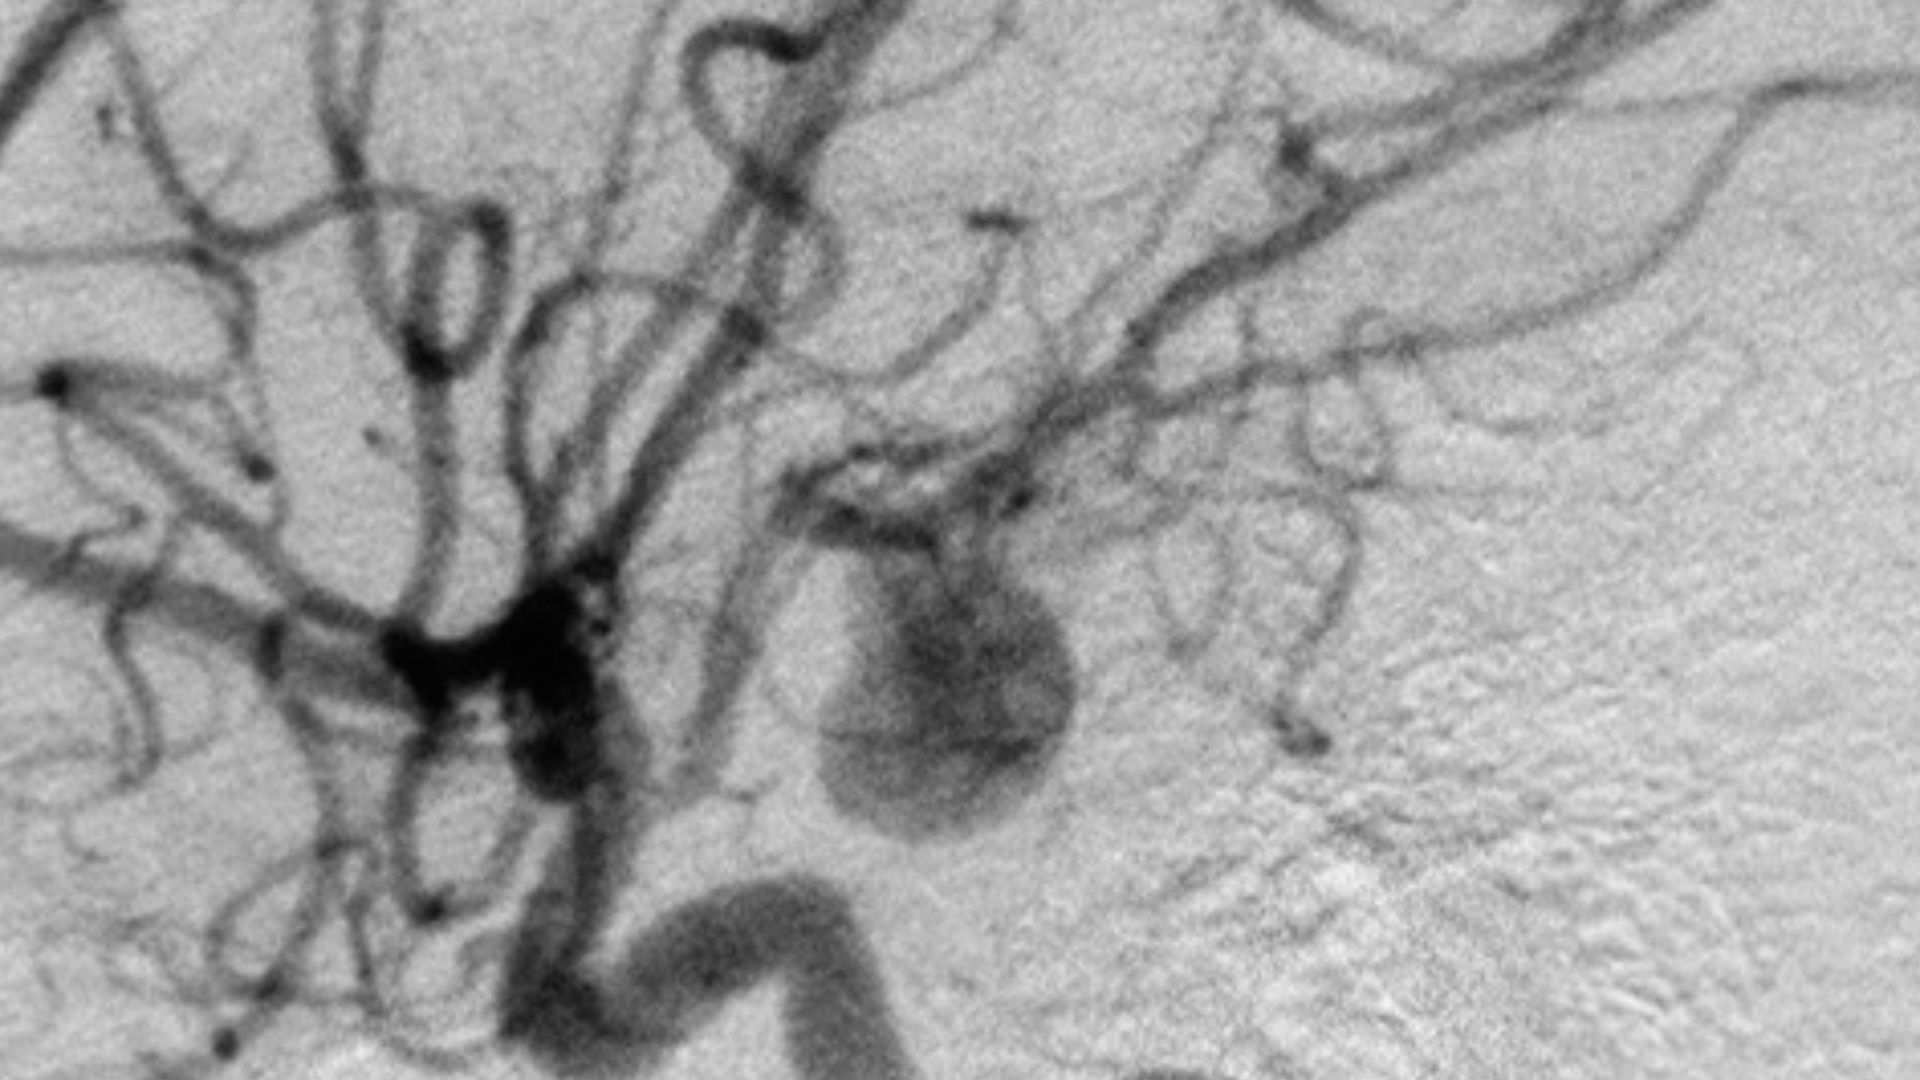

A Life-Threatening Diagnosis

Clarke had suffered a subarachnoid hemorrhage—a type of stroke caused by a brain aneurysm. It’s a condition that can be fatal without immediate treatment. Within a matter of hours, her life had shifted from rising star to fighting to survive.

Another Aneurysm Was Still There

Doctors had discovered a second aneurysm during her initial treatment. It was smaller at the time and didn’t require immediate surgery—but it didn’t go away. It remained a constant risk in the background of her life.

A couple years later, in 2013, scans showed that the second aneurysm had grown. This time, there was no waiting. Clarke once again faced the possibility of losing her life—just as her career was reaching even greater heights.

Another Surgery—And Another Risk